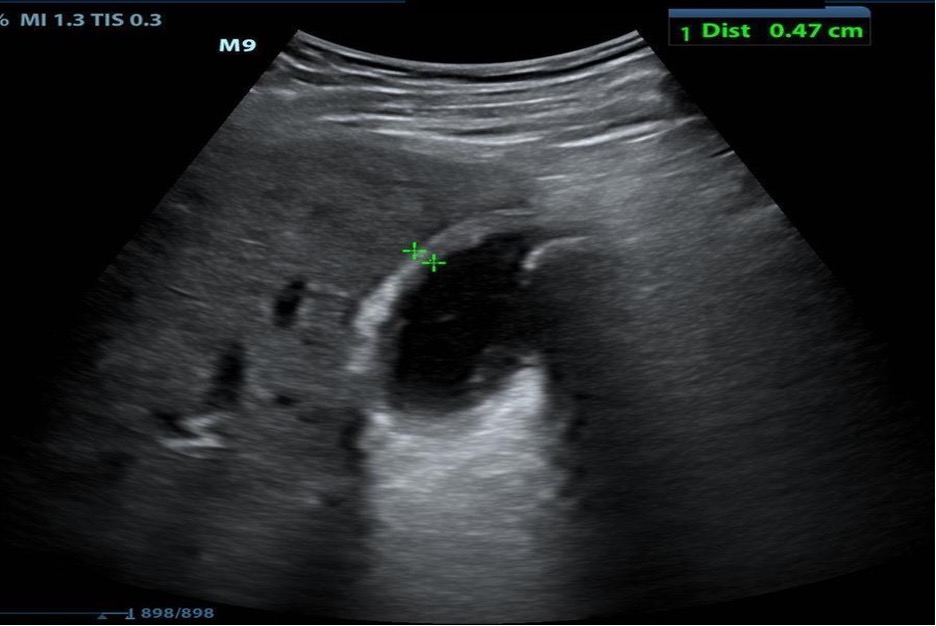

Urinary Tract

Flank pain or renal colic due to the presence of ureterolithiasis is a common presenting complaint in the emergency department. The presence of hydronephrosis (Figure 25) identified with ultrasound in patients with classic symptoms of renal colic, such as flank pain and hematuria, is highly suggestive of ureterolithiasis as the cause of the patient’s symptoms.

Figure 25. Moderate hydronephrosis of the right kidney (top image) upstream from the ureterovesicular junction stone marked with calipers seen near the bladder (bottom) (Images courtesy of Matthew Lohse, MD. Baylor Scott & White-Temple).